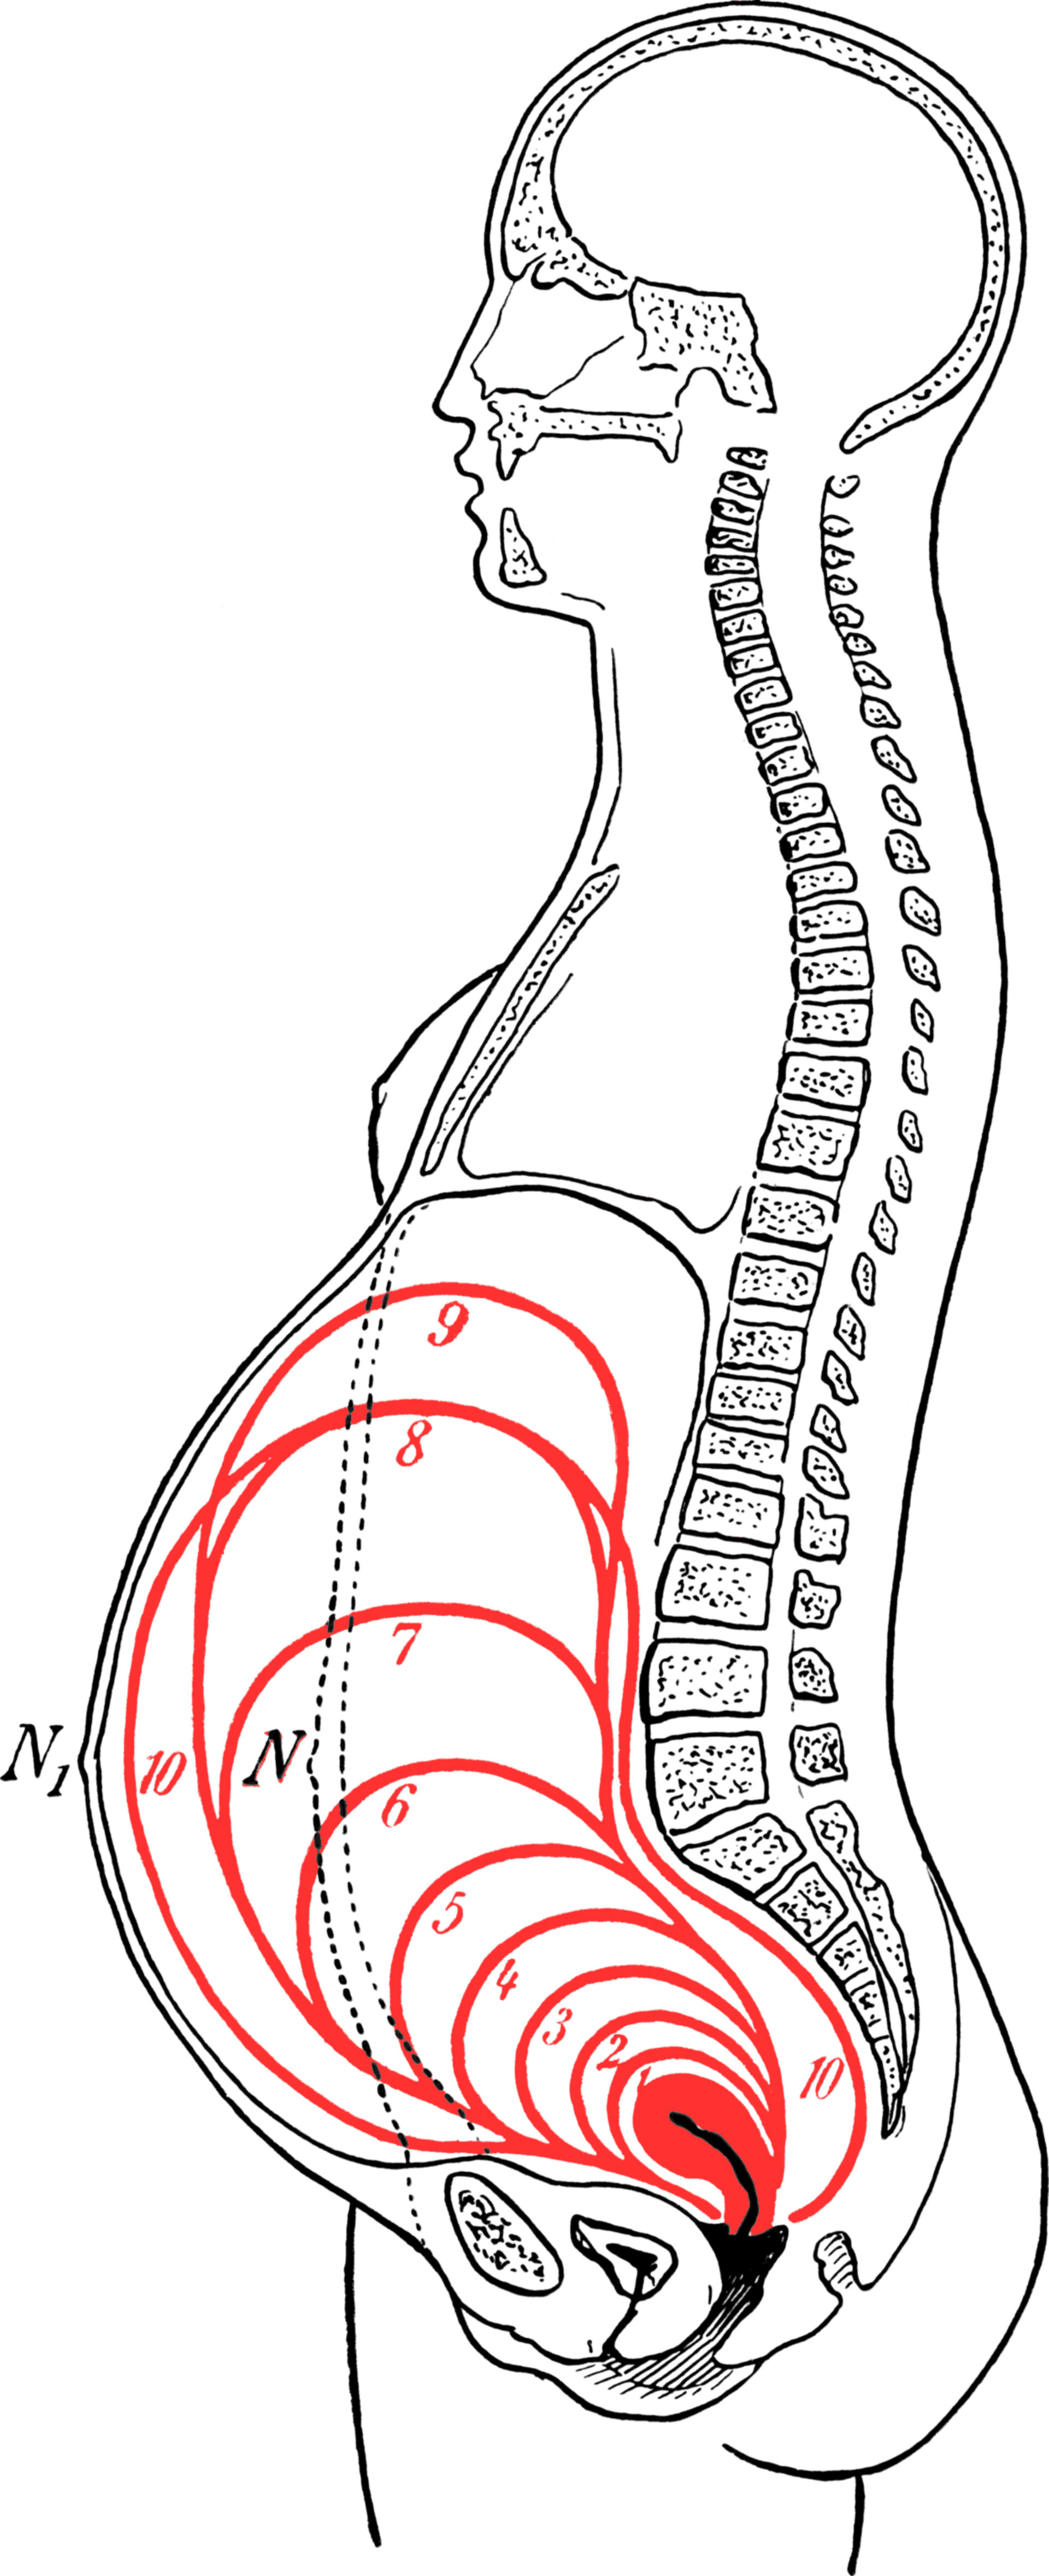

Where Is Uterus During Pregnancy

Where Is Uterus During Pregnancy

https://dccdn.de/www.doccheck.com/data/99/ju/rr/kh/eu/f6/grossedergebarmutterindeneinzelnemonatenderschwangerschaft_lg.jpg

More picture related to Where Is Uterus During Pregnancy

Pregnant Uterus

Pregnant Uterus

Uterus Pregnancy Length

Uterus Pregnancy Length